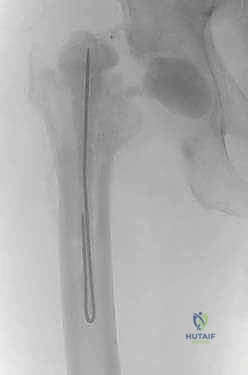

4. تحضير ووضع "الفاصل المحمل بالمضادات الحيوية" (Antibiotic Spacer)

ما هو الفاصل الإسمنتي؟ هو جهاز مؤقت يتم تشكيله أثناء العملية باستخدام "إسمنت العظام" الطبي (Polymethylmethacrylate - PMMA).

* السر الطبي: يتم خلط هذا الإسمنت بجرعات عالية جداً من المضادات الحيوية (مثل الفانكومايسين والتوبيمايسين) التي تتحمل الحرارة العالية الناتجة عن تصلب الإسمنت.

* آلية العمل: بمجرد وضعه داخل تجويف الورك، يبدأ الفاصل في إطلاق تركيزات هائلة من المضادات الحيوية موضعياً داخل المفصل، بتركيز يفوق مئات المرات ما يمكن تحقيقه عبر الدم، مما يقضي على أي بكتيريا متبقية في العظم.

* أنواع الفواصل:

* فواصل ثابتة (Static): كتل إسمنتية تمنع الحركة تماماً، تُستخدم في حالات فقدان العظم الشديد.

* فواصل مفصلية (Articulating): تشبه المفصل الحقيقي، تسمح للمريض بثني الورك والمشي الخفيف، مما يحافظ على مرونة العضلات ويسهل الجراحة الثانية. وهو النوع الذي يفضله د. هطيف متى ما كانت حالة العظم تسمح بذلك.